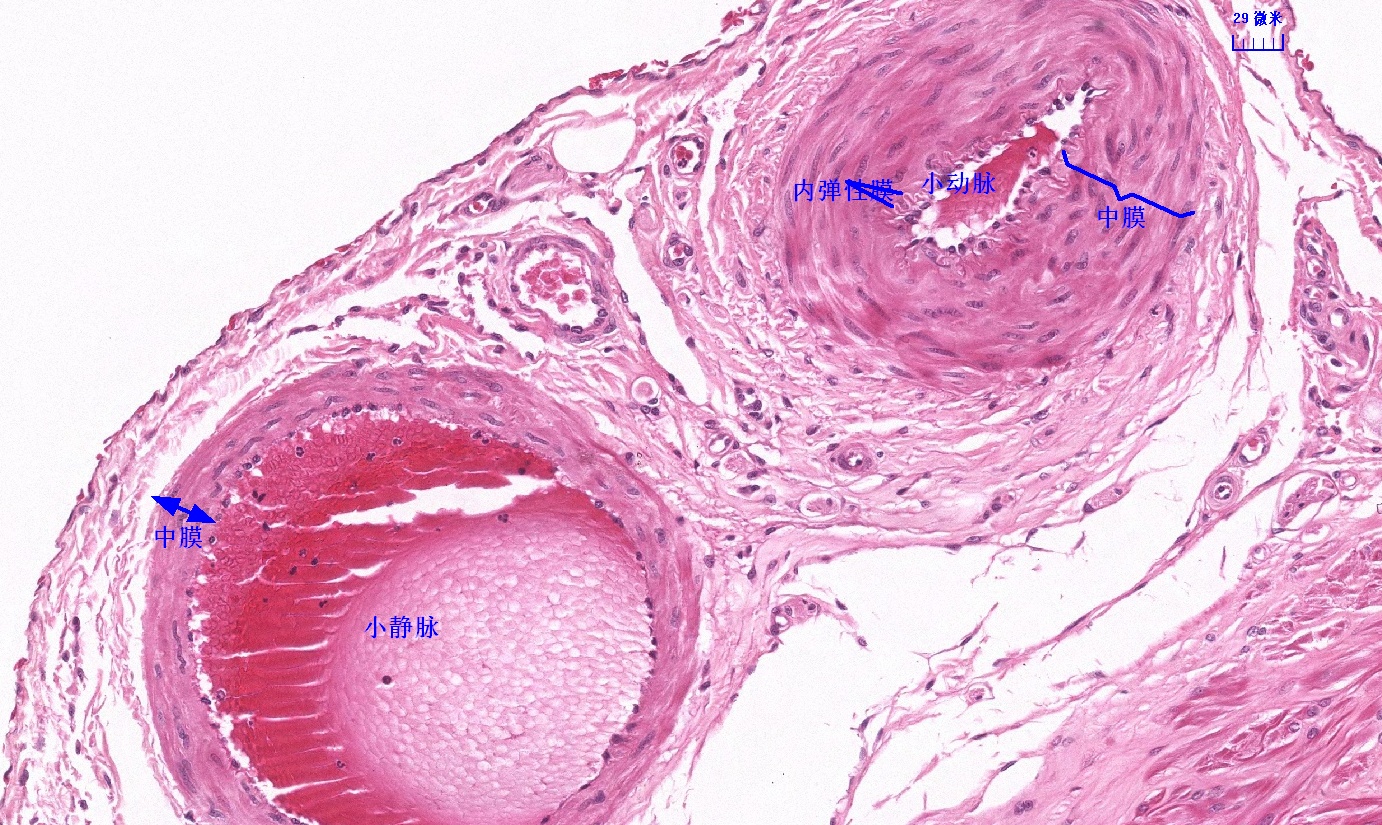

6.1 循环系统切片库